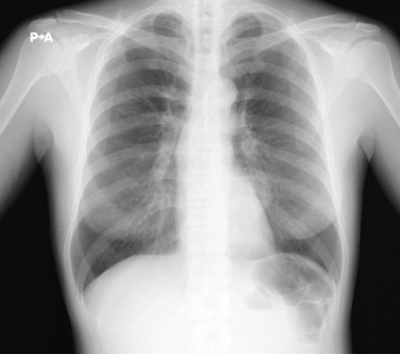

23歳の女性。入社時の健康診断の胸部エックス線写真で異常陰影を指摘されたため産業医から紹介受診となった。自覚症状はない。喫煙歴はない。胸部エックス線写真を別に示す。

次に行うべき検査はどれか。2つ選べ。